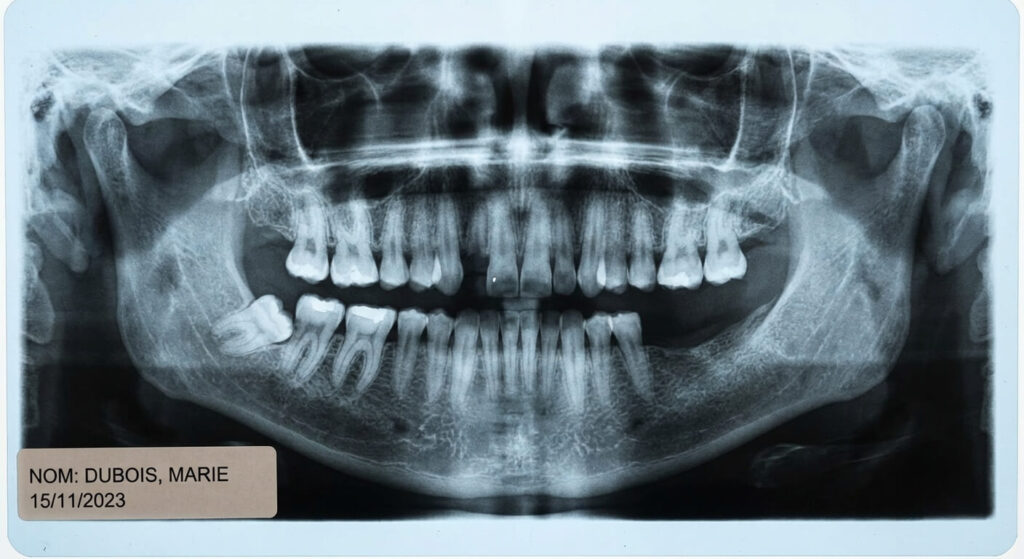

| Gencive arrière rouge, enflée, goût de pus. | Péricoronarite sur dent de sagesse émergente. | Examen clinique + Radiographie Panoramique. |

| Blessure et ulcère sous le dentier arrière. | Frottement de la prothèse sur la pointe de la dent. | Radiographie rétro-alvéolaire ciblée. |

| Décharges électriques vers la lèvre inférieure. | Compression du nerf maxillaire par la racine. | Scanner dentaire 3D (Cone Beam). |